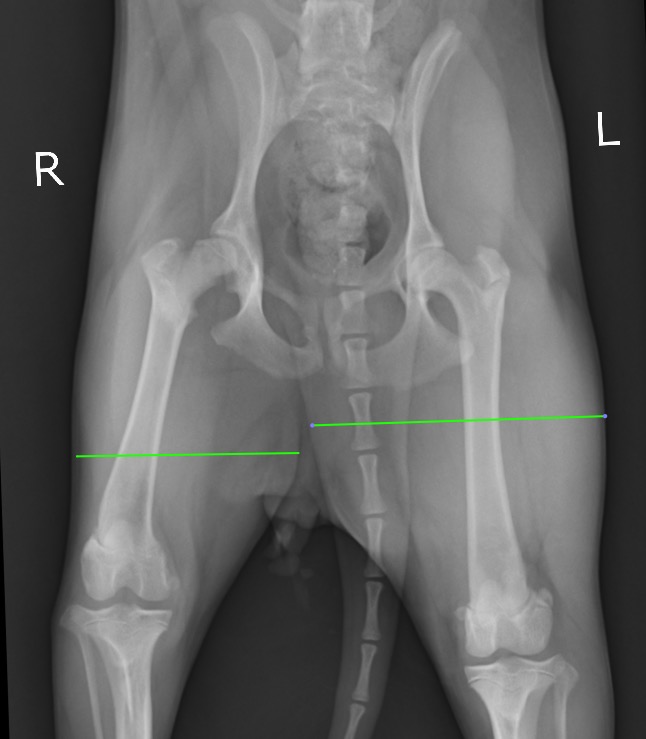

また右の大腿部の筋肉量が左に比べてだいぶ細いこともよく分かります。(緑線)

痛みのある右の後ろ足をかばいなるべく体重をかけず使わないように生活していた結果の筋萎縮だと考えられます。

右の大腿部の廃用性筋萎縮